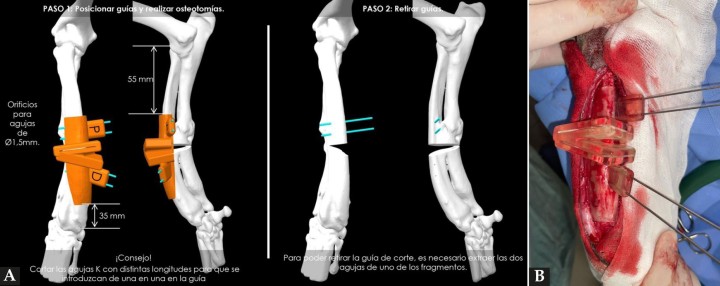

Tradicionalmente, la planificación de estas correcciones se realizaba sobre radiografías que servían de soporte para calcular y localizar el CORA. Sin embargo, la rectificación de la deformidad que se obtenía con esta metodología, usando tan solo radiografías, no ofrecía el mismo grado de rigor que con las propuestas actuales, ni permitía la corrección en todas las orientaciones. Con el avance de la tecnología (incorporación de la TC) y la experiencia en el ámbito de la traumatología y ortopedia humana, empieza a tener relevancia el empleo de guías quirúrgicas específicas. Estos dispositivos permiten reducir el tiempo de cirugía, aumentar la precisión (obteniendo mejores resultados) y disminuir errores en quirófano. Estas guías están diseñadas para encajar perfectamente sobre el hueso, puesto que se ha copiado la geometría de la TC, contando con dos ranuras para introducir la hoja de la sierra y realizar los cortes, con la orientación necesaria para obtener la corrección prevista (Fig. 3A).[ Worth AJ, Crosse KR, Kersley A. Computer-assisted surgery using 3D printed saw guides for acute correction of antebrachial angular limb deformities in dogs. Vet Comp Orthop Traumatol 2019; 32(3): 241-249. [PubMed] , Hall EL, Baines S, Bilmont A et al. Accuracy of patient-specific three-dimensional-printed osteotomy and reduction guides for distal femoral osteotomy in dogs with medial patella luxation. Vet Surg 2019; 48(4): 584-591. [PubMed] ] En este caso, se planificó la corrección para modificar la deformidad angular que sufrían cúbito y radio, adaptando lo más posible la anatomía de estos huesos a su conformación espacial deseable (en sus tres planos anatómicos: sagital, frontal y transverso), que en ocasiones es la del miembro contralateral, si en este no hay deformidad o es mínima.

(A) Reproducción en 3D de la aplicación de la guía quirúrgica que permitirá realizar los cortes adecuados sobre el cúbito y radio (ostectomía) posibilitando así la mejor alineación de estos huesos. (B). Imagen de la colocación de la guía quirúrgica durante la intervención.

Figura 3

Tras exponer el radio, el primer paso consistió en posicionar la guía de corte en la zona cráneo/medial del área media/distal de este hueso (según lo planificado), fijando temporalmente su posición con la ayuda de 4 agujas introducidas a través de los orificios proximales y distales de la guía. Una vez fijada, se realizaron los cortes con una sierra oscilante recta a través de las dos ranuras del dispositivo (Fig. 3B). A continuación, en un segundo paso, se retiró la guía de corte y se sustituyó por la de alineación, empleando el mismo sistema de fijación con agujas para conseguir la reducción de los fragmentos, según la planificación prevista. Esta segunda guía está diseñada para poder mantener en la posición adecuada los fragmentos mientras se estabilizan con la placa principal (Fig. 4A). En este caso, se colocó en primer lugar y como principal una placa bloqueada tipo puente que aplicamos sobre el área craneal del radio, con tornillos de 3,5 mm de diámetro (Fig. 4B). Posteriormente, colocamos otra placa de bloqueo auxiliar, de tipo multiorificios por el aspecto medial, con tornillos de 2,7 mm de diámetro para reforzar la estabilización.